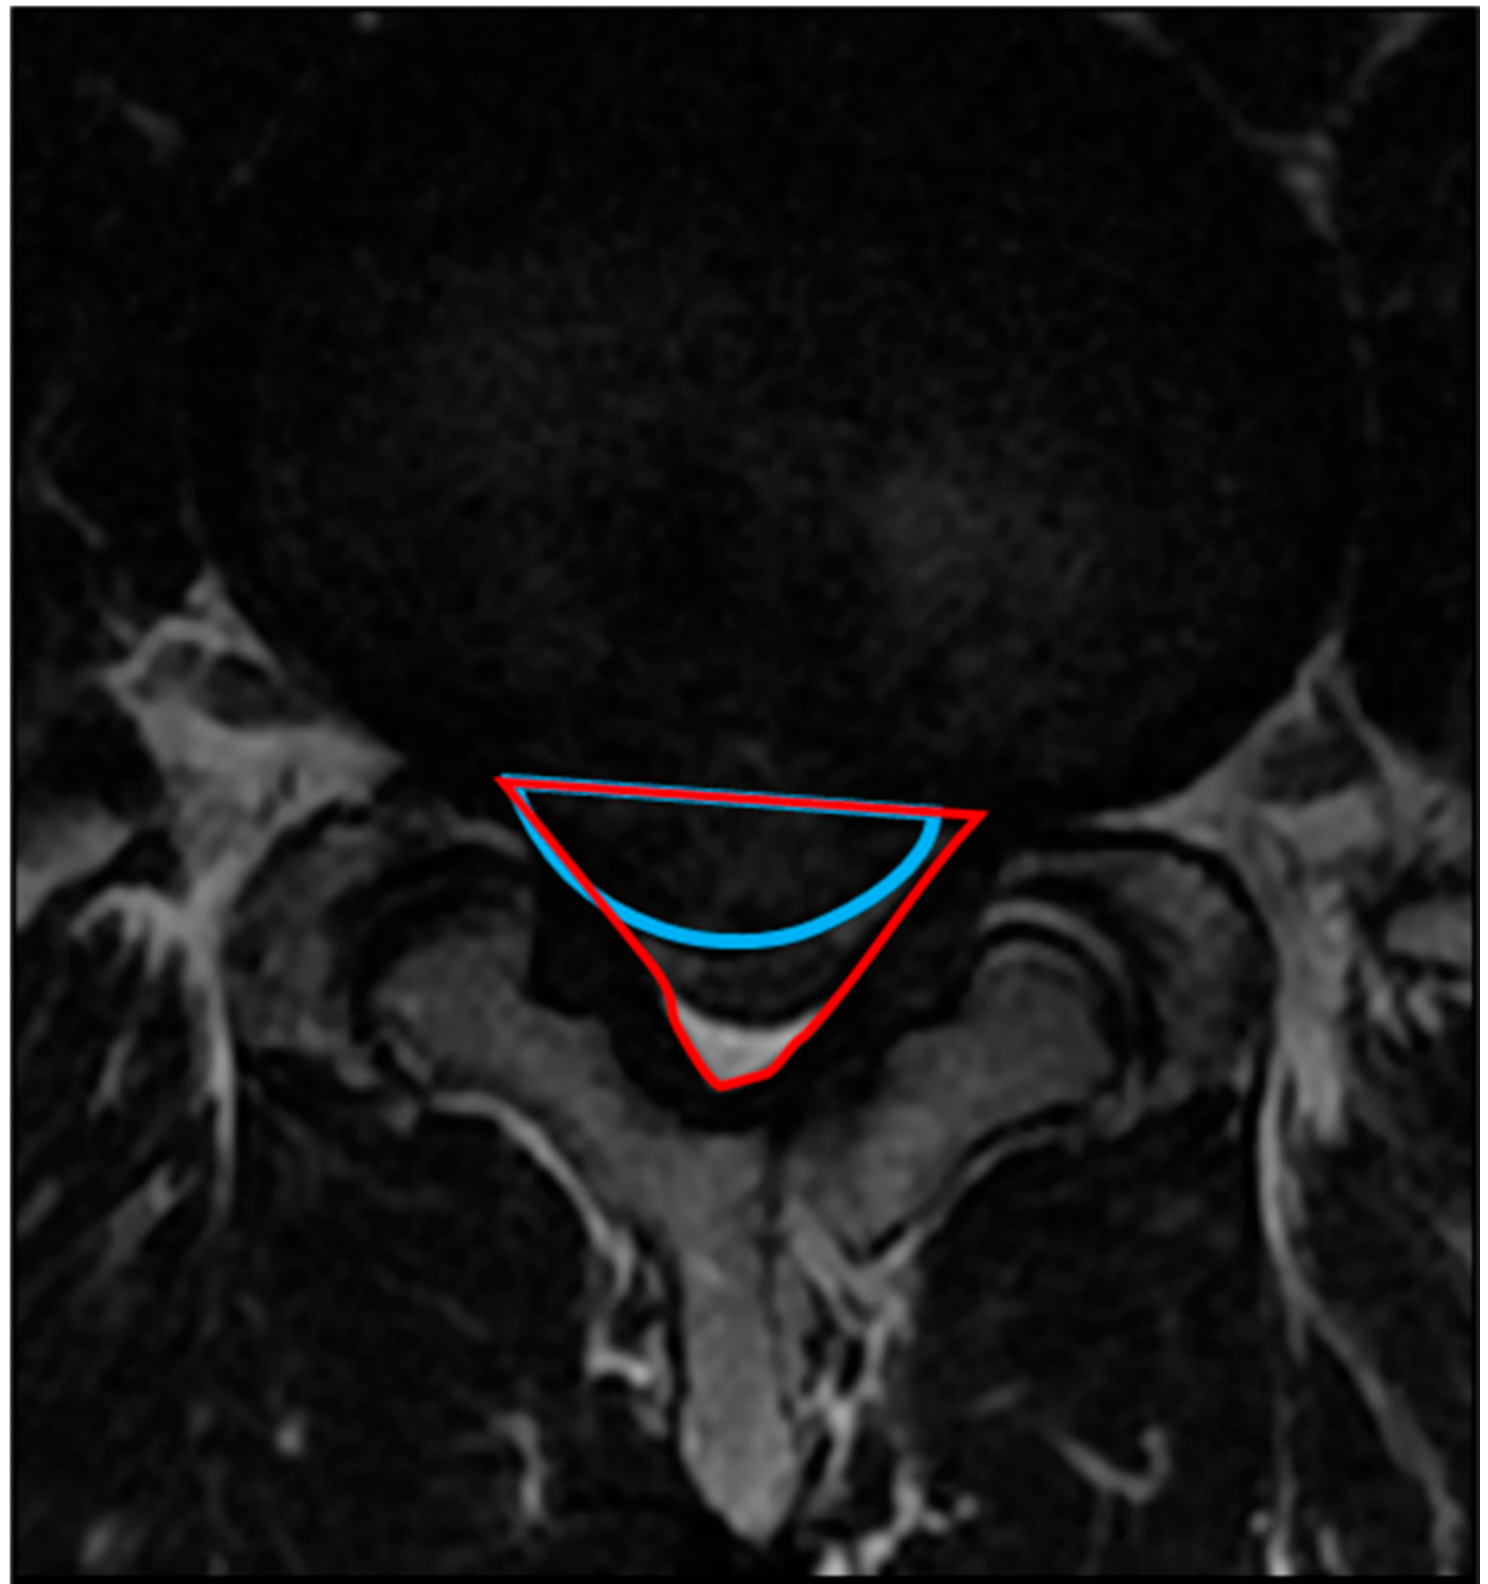

2.4.2. Occupancy Ratio of the Spinal Canal by the Protruded Nucleus Pulposus (NP)